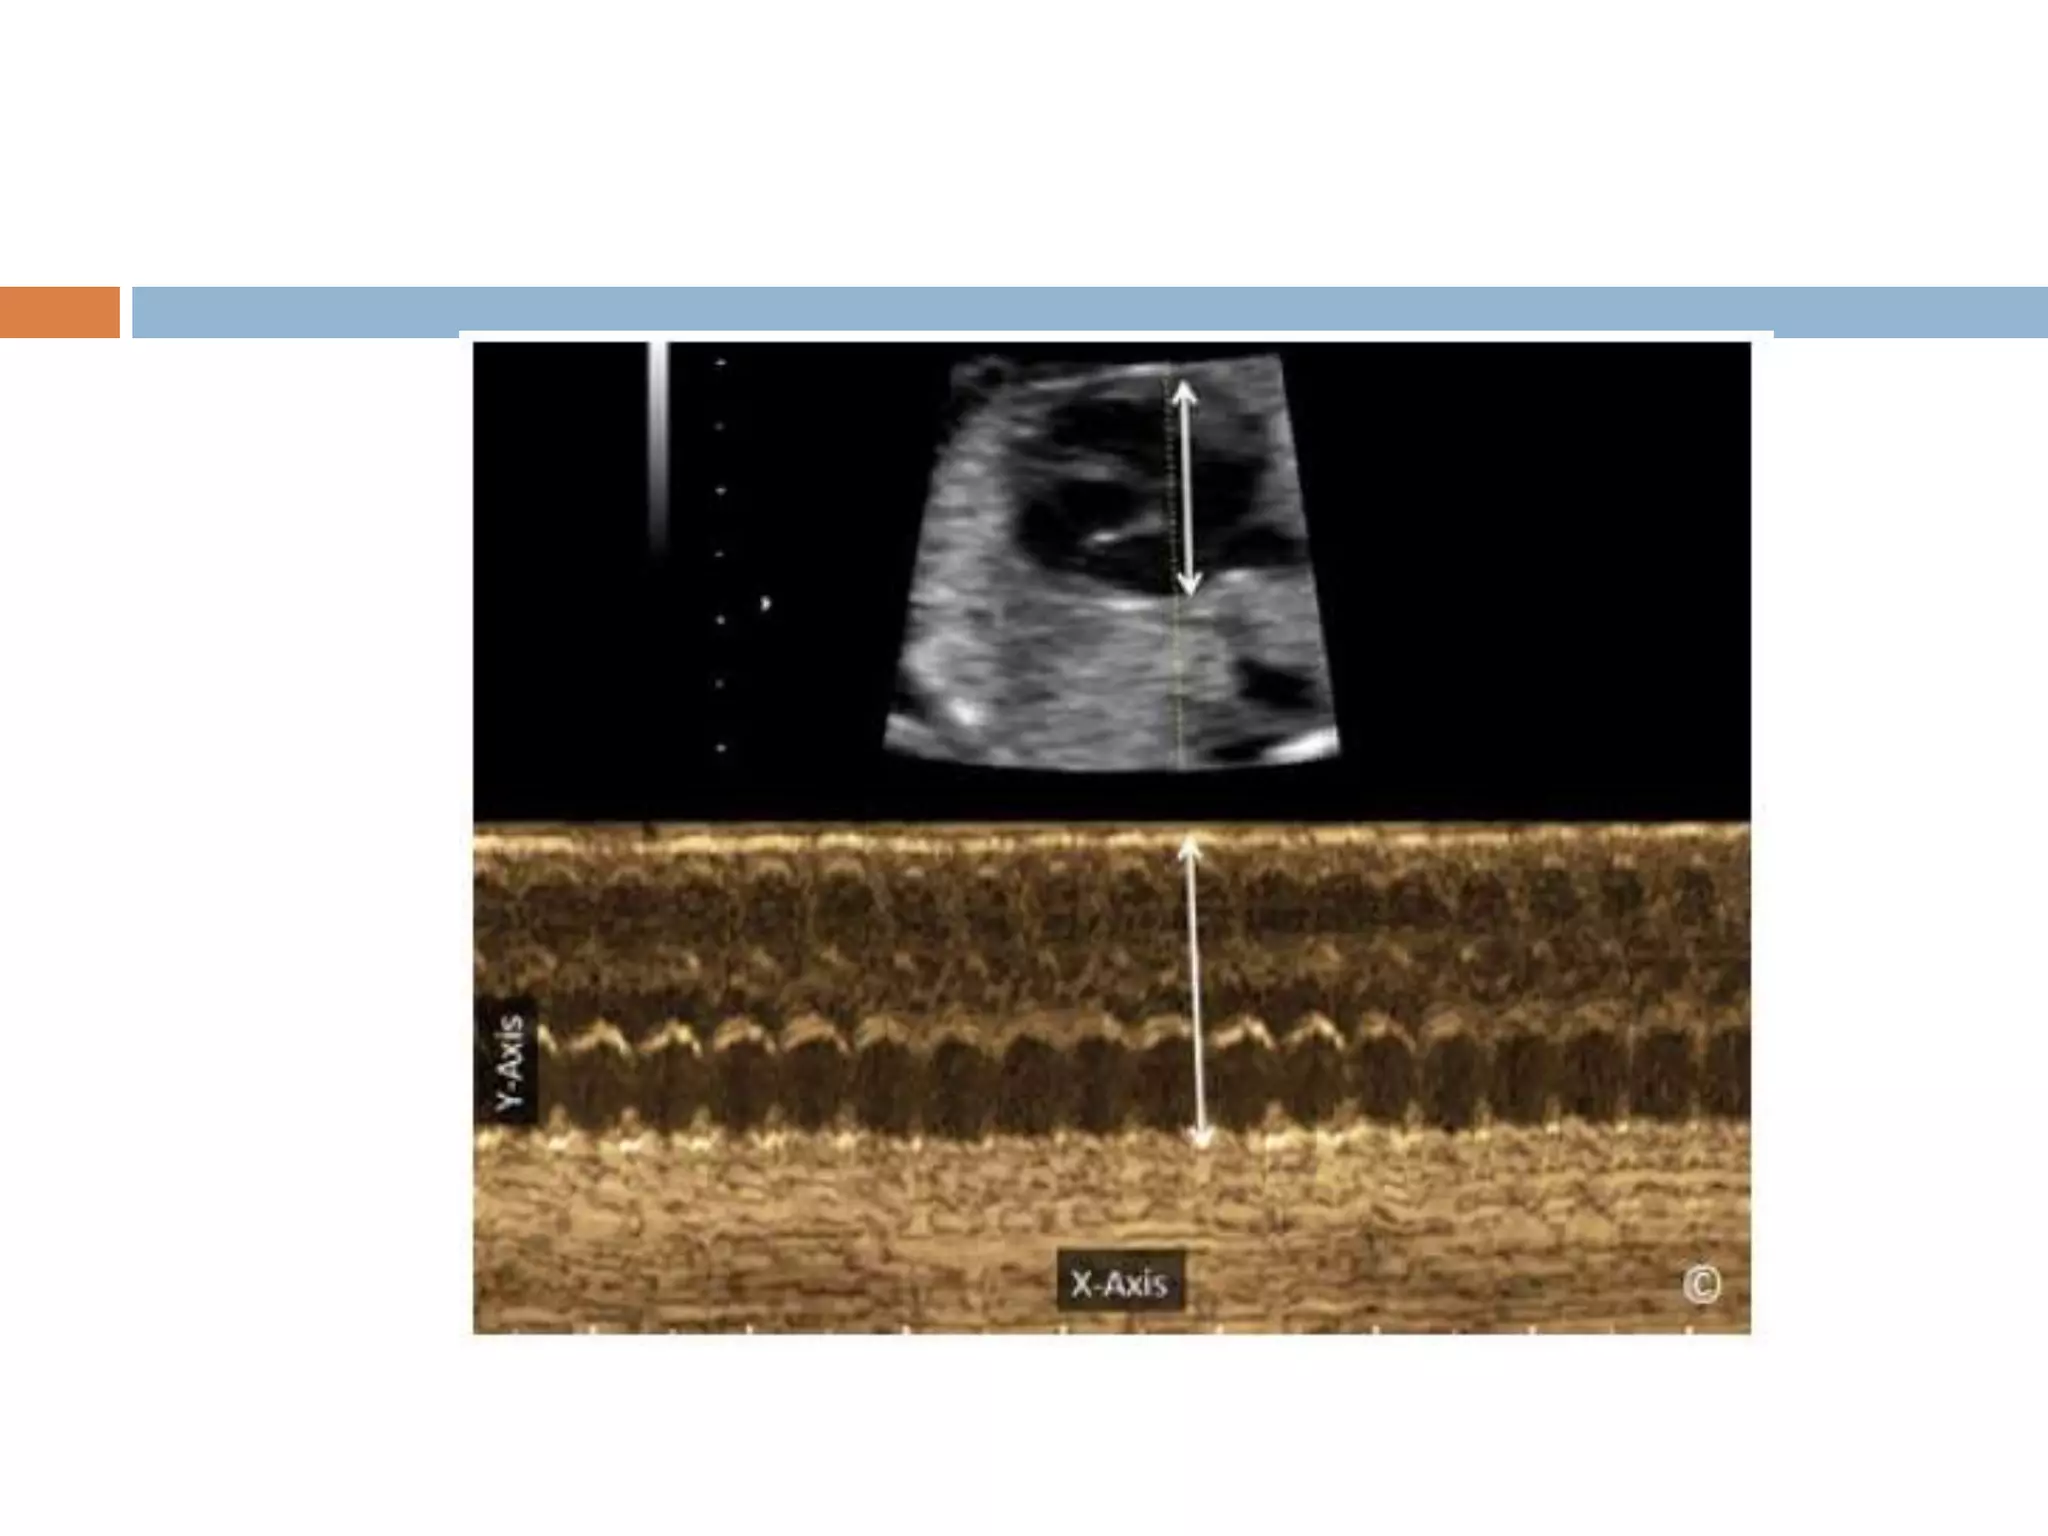

M-mode:

 M stands for motion.

 A sequence of scans is made along a fixed

line in the body.

 The echos are represented as lines on the

screen.

 This enables doctors to see and measure

range of motion, as the move relative to the

probe.

Four different modesof U/S are used in medical imaging(cont.) M-mode:  M stands for motion.  A sequence of scans is made along a fixed line in the body.  The echos are represented as lines on the screen.  This enables doctors to see and measure range of motion, as the move relative to the probe.